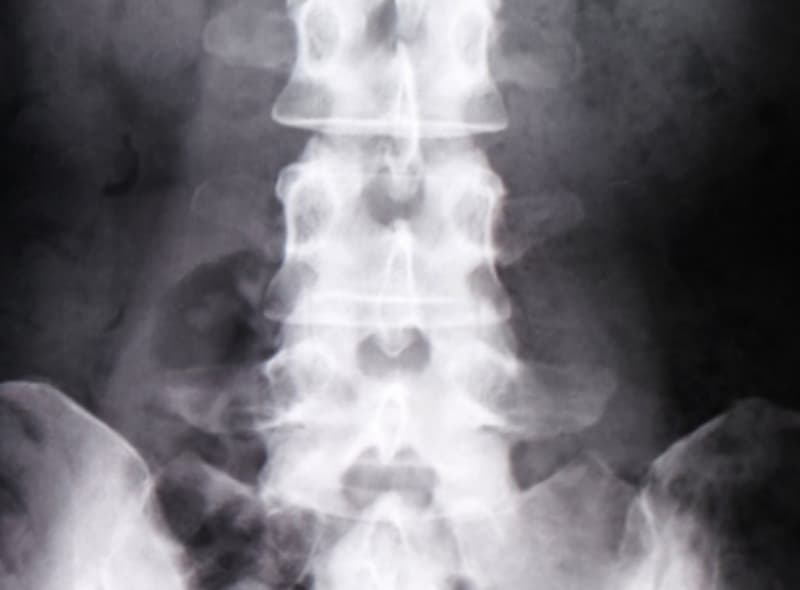

腰部のレントゲン検査

腰部に骨折が無いかを事前に確認します。もし以前に骨折がある場合、骨密度の値が高く出る場合があるので、事前に確認します。

腰椎のレントゲン検査後に合わせ検査をします。

骨塩定量測定(DXA法)検査当日に、腰椎のレントゲン検査の結果と合わせて骨密度検査結果をご説明いたします。